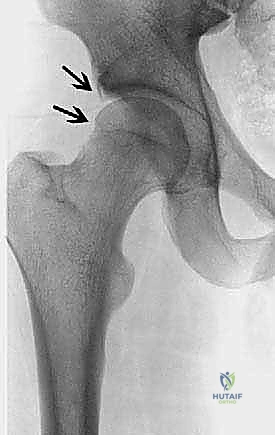

- الأشعة السينية (X-rays): لتقييم شكل العظام، قياس "زاوية ألفا" (Alpha Angle)، وتحديد وجود نتوءات الكامة أو الكماشة.

يحدث هذا النوع عندما لا يكون رأس عظم الفخذ كروياً بشكل مثالي. بدلاً من ذلك، تتكون نتوءات عظمية إضافية عند منطقة التقاء رأس وعنق الفخذ. هذا الشكل غير الدائري يجعله يحتك بقوة بحافة التجويف (الحُق) أثناء الحركة، مما يؤدي إلى "كشط" وتمزيق الغضروف والشفا الحقي. هذا النوع شائع جداً بين الشباب والرياضيين الذكور.

2. انحشار الكماشة (Pincer Impingement)